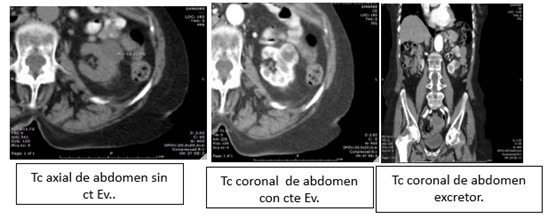

La Categoría IV presenta captación de un componente sólido intra quístico, muestra realces nodulares fuera de la pared y de los septos interpuestos en el área quística compleja, calcificaciones gruesas, vascularizadas con un importante realce con contraste yodado IV. En realidad, son lesiones malignas con componente quístico. Se trata de neoplasias quísticas, y precisan cirugía y estadificación.(19, 21) (Anexos 11 y 12).

- Bosniak IV: finalmente, el 3% de los quistes (15 pacientes) fueron clasificados como Bosniak IV, de los cuales 12 pacientes eran de sexo masculino y 3 de sexo femenino. Estos quistes presentaron características de neoplasia quística renal y carcinoma renal quístico, lo que requirió intervención quirúrgica inmediata (Anexo 23).